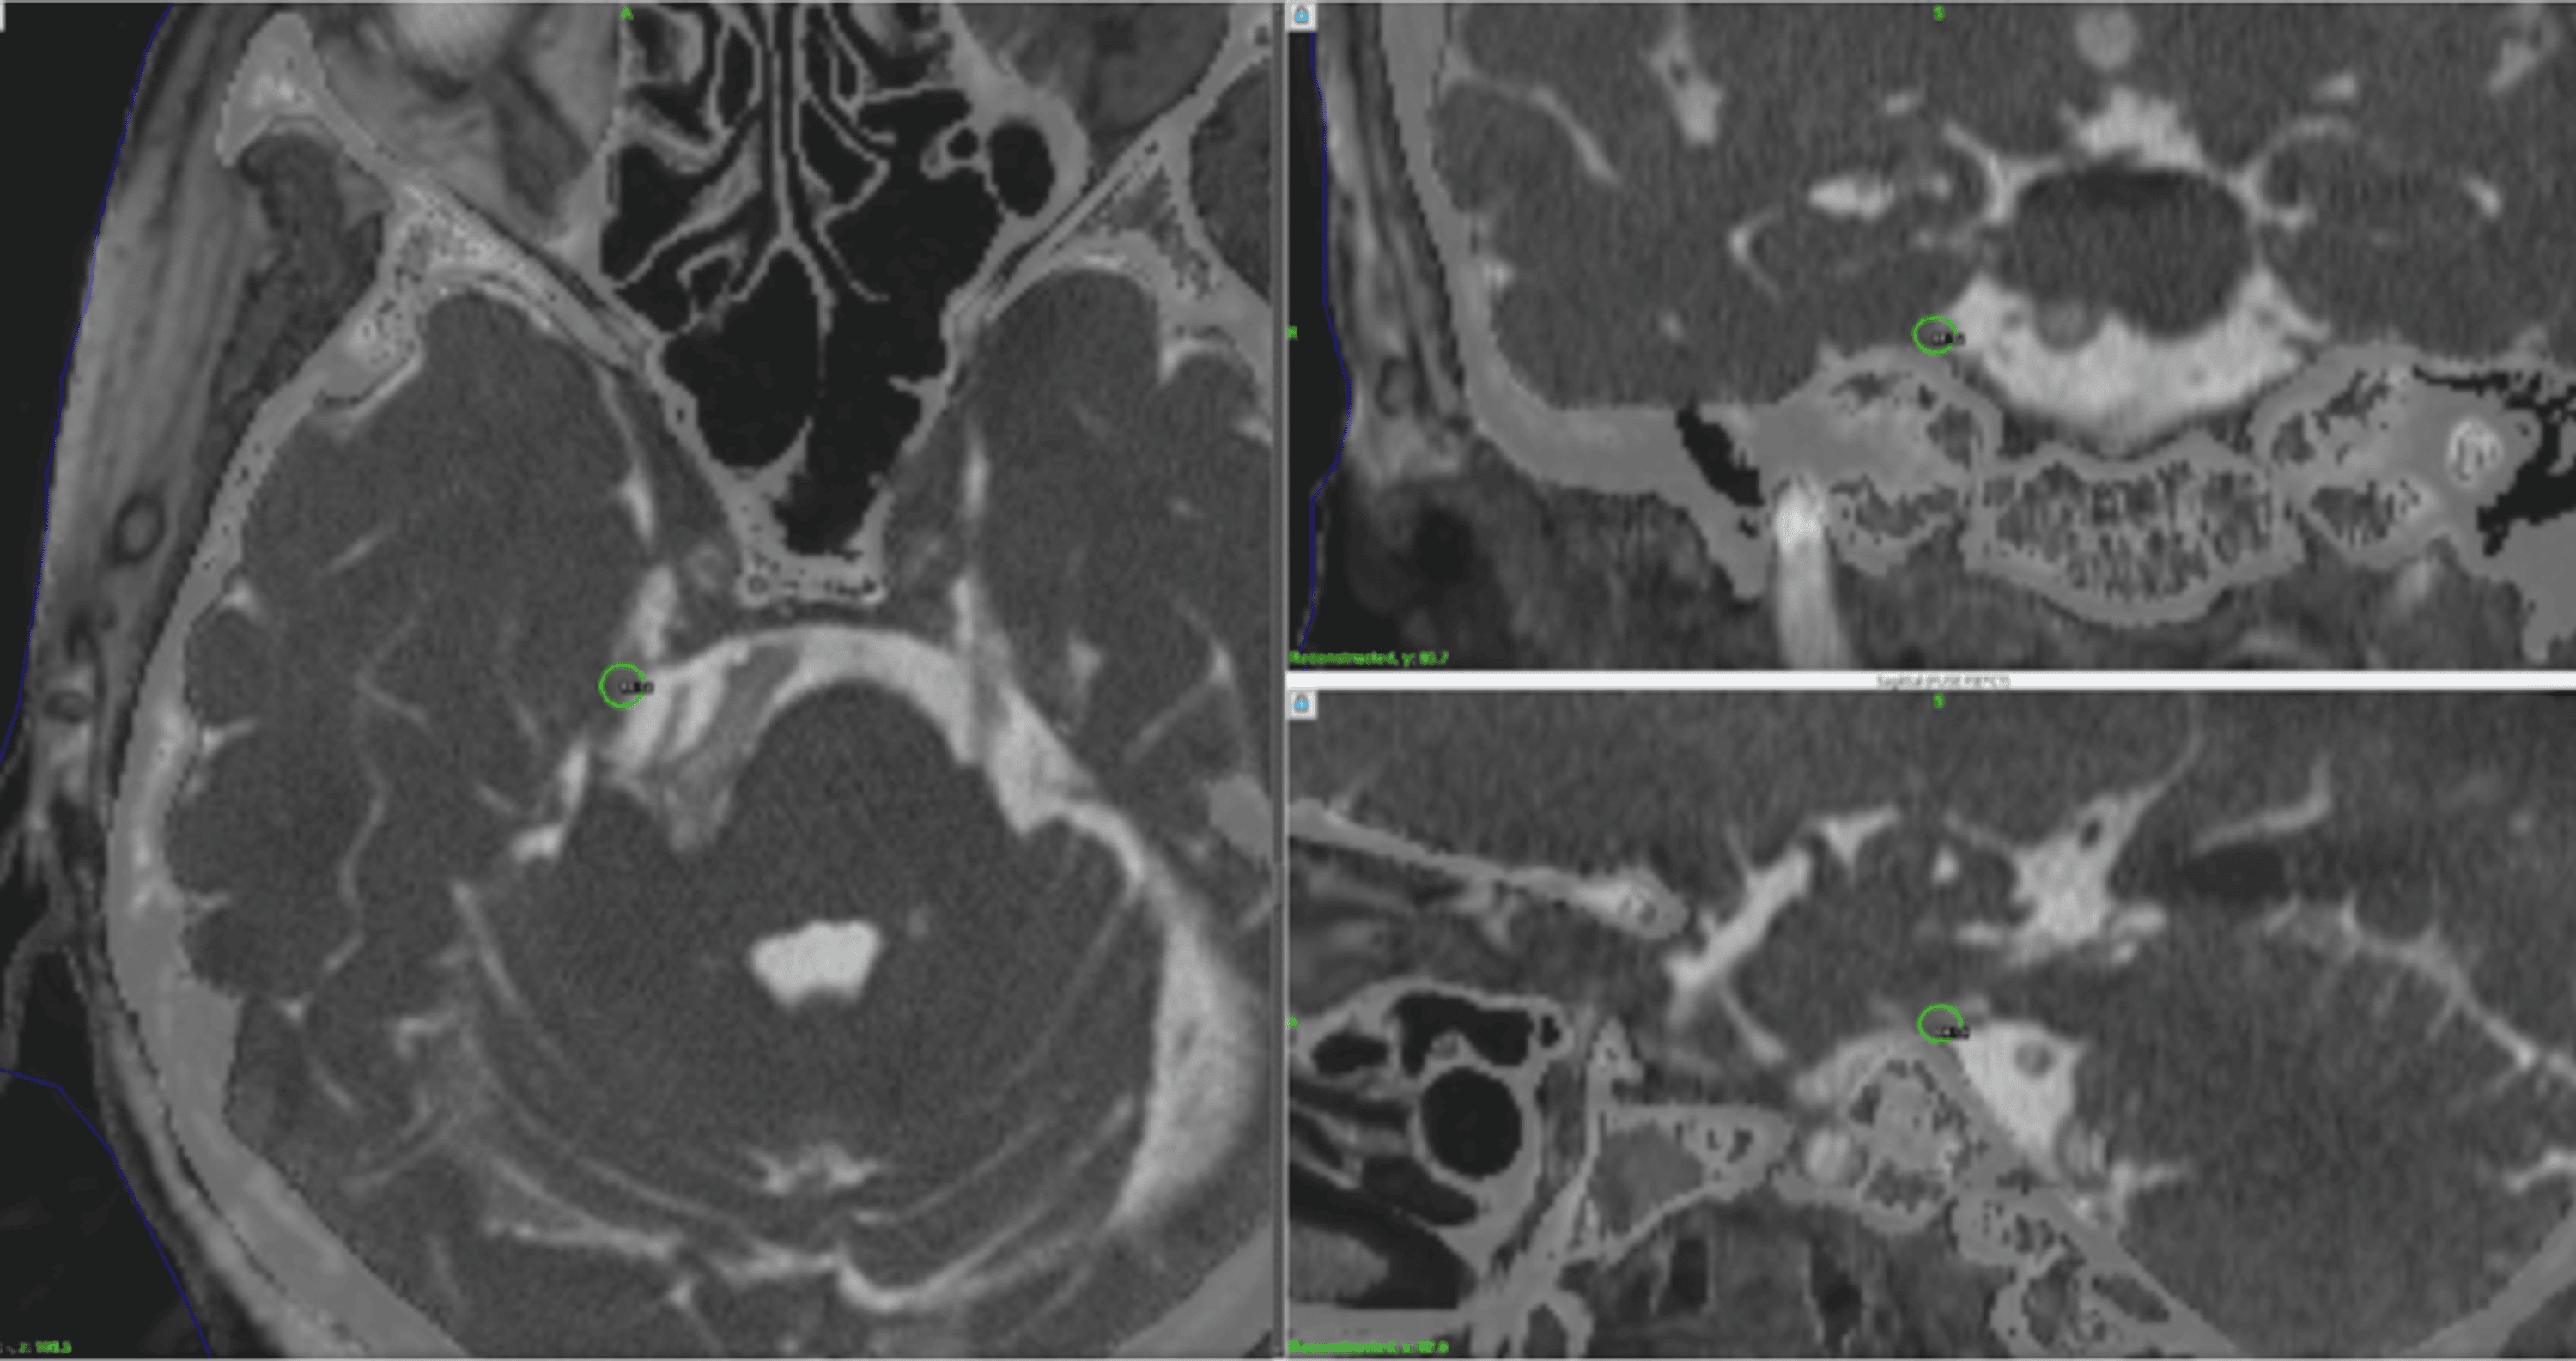

From www.semanticscholar.org

Figure 1 from Threedimensional Fast Imaging Employing Steadystate Acquisition Stereotactic Radiosurgery Trigeminal Neuralgia stereotactic radiosurgery is an effective treatment option for trigeminal neuralgia (tn), with frameless. the aims of this systematic review are to provide an objective summary of the published literature specific to the treatment of classical. The aims of this systematic review are to provide an objective summary of the published. stereotactic surgery uses focused radiation to damage. Stereotactic Radiosurgery Trigeminal Neuralgia.